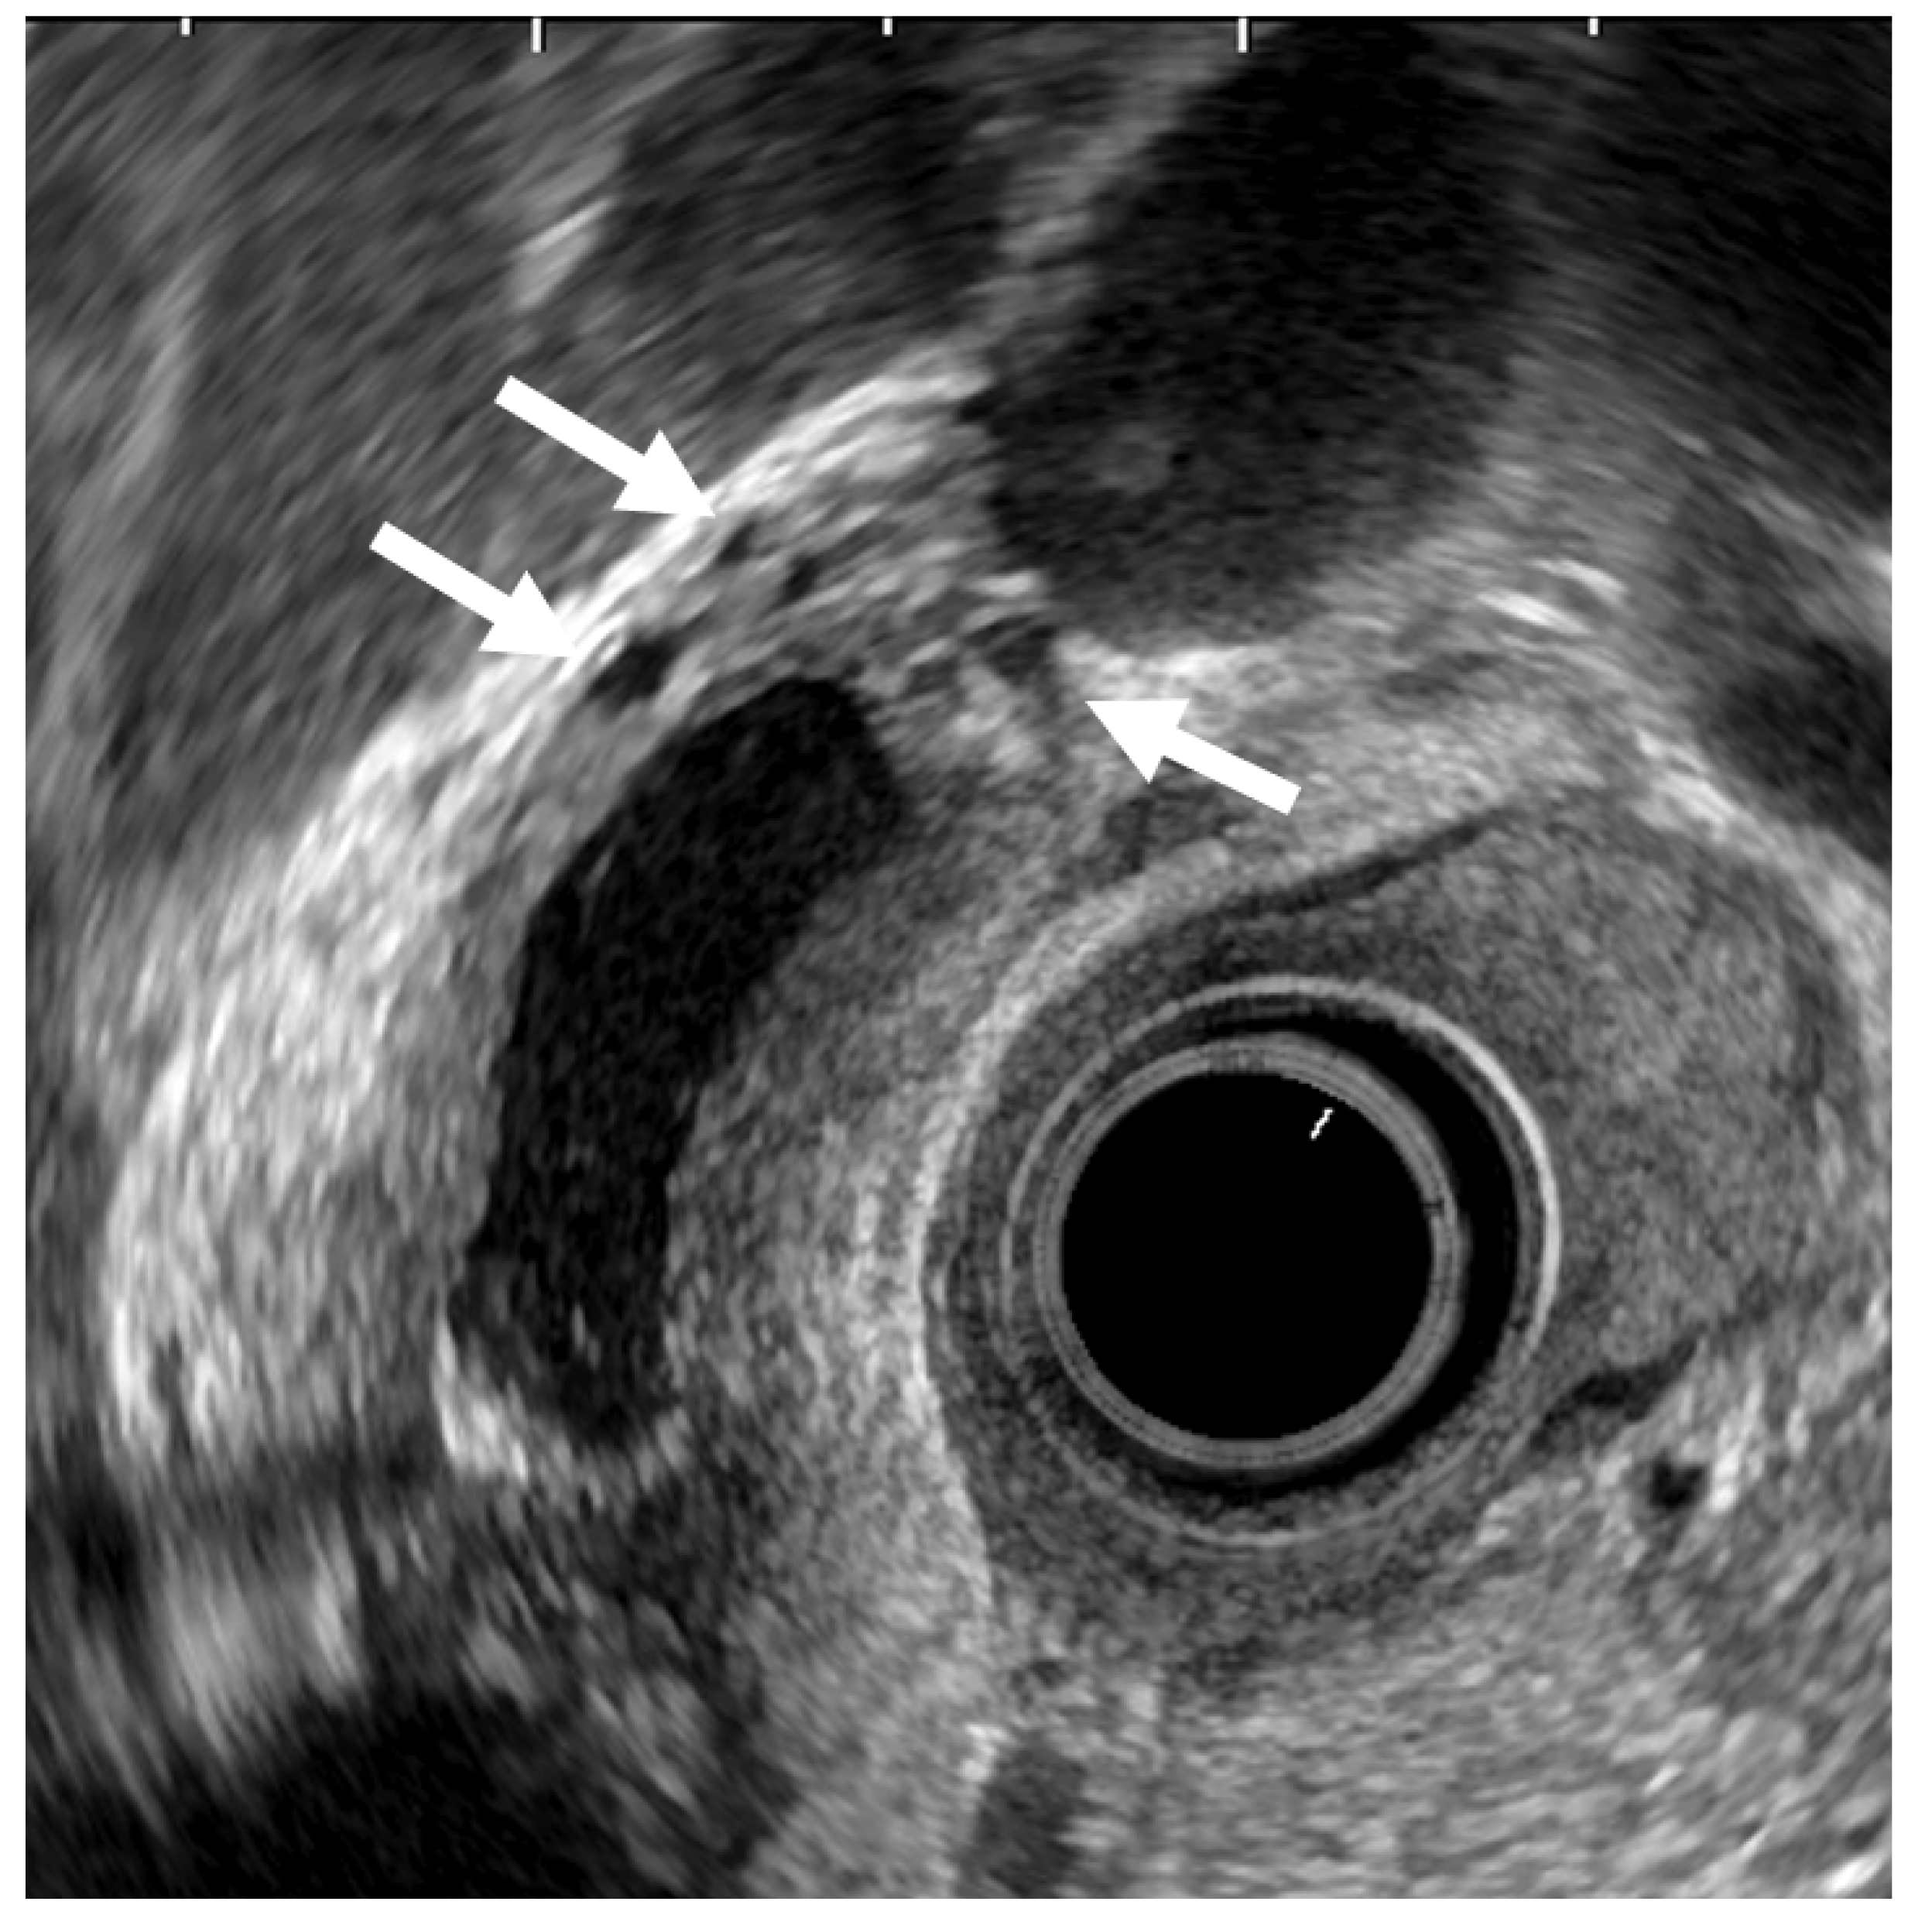

ADM can sometimes mimic GB carcinoma. The layers of a thickened GB wall are usually preserved in ADM, but there are microcysts with bright echoes arising from the cystic spaces. The thickened wall has a smooth surface but occasionally exhibits surface irregularity, reflecting hyperplastic changes. A key point in its diagnosis is the confirmation of the presence of cystic anechoic spots reflecting RAS inside the thickened wall (Figure 4) [26].

Figure 4.

EUS image of ADM (diffuse type). The GB wall is diffusely thickened, and the layers of a thickened GB wall are preserved. Some anechoic areas (arrows) are visualized in the GB thickened wall.